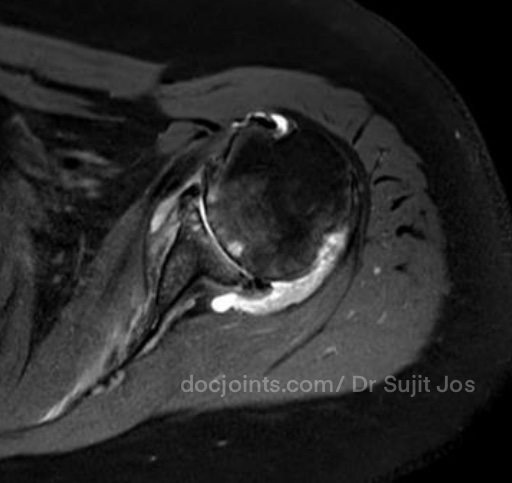

On presentation to the OP, the lifting power of the shoulder was significantly affected on strength testing (emply can test indicating supraspinatus tendon tear) and outward rotation was very weak (indicating Infraspinatus tendon tear). Xray and MRI images attached below.

There was significant fatty infiltration of the rotator cuff muscles along with osteoarthritis of the shoulder joint. Treatment options were discussed. Reverse shoulder arthroplasty is the modern treatment for this type of pathology, which can restore muscle function by orienting the shoulder centre of rotation in such a way that the Deltoid muscle can help in elevating the limb from neutral position (Read more about Reverse shoulder replacement >>).